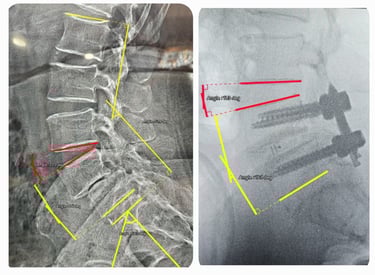

Spine Fusion Surgery MIS TLIF

Stitch-less techniques for faster healing.

Degenerative Scoliosis Correction

Gentle corrections for lasting posture improvement.